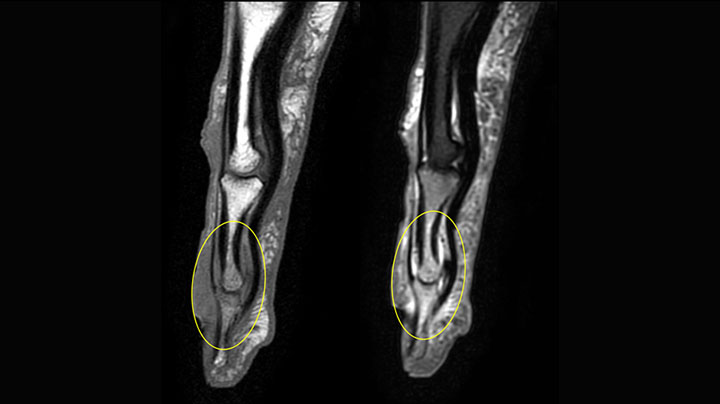

MRI examination on Prodiva 1.5T of a 72-year-old female with a malignant melanoma in the ankle. mDIXON TSE provides excellent fat suppression, without the distortion that is often seen at such extremities.